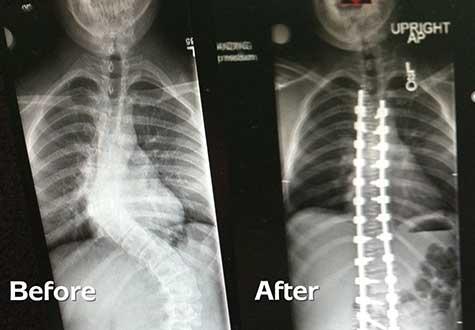

While scoliosis can’t be prevented, severe scoliosis can be avoided through early treatment. Bachmann says that bracing, physical therapy, and even surgery are all useful tools for treating scoliosis.